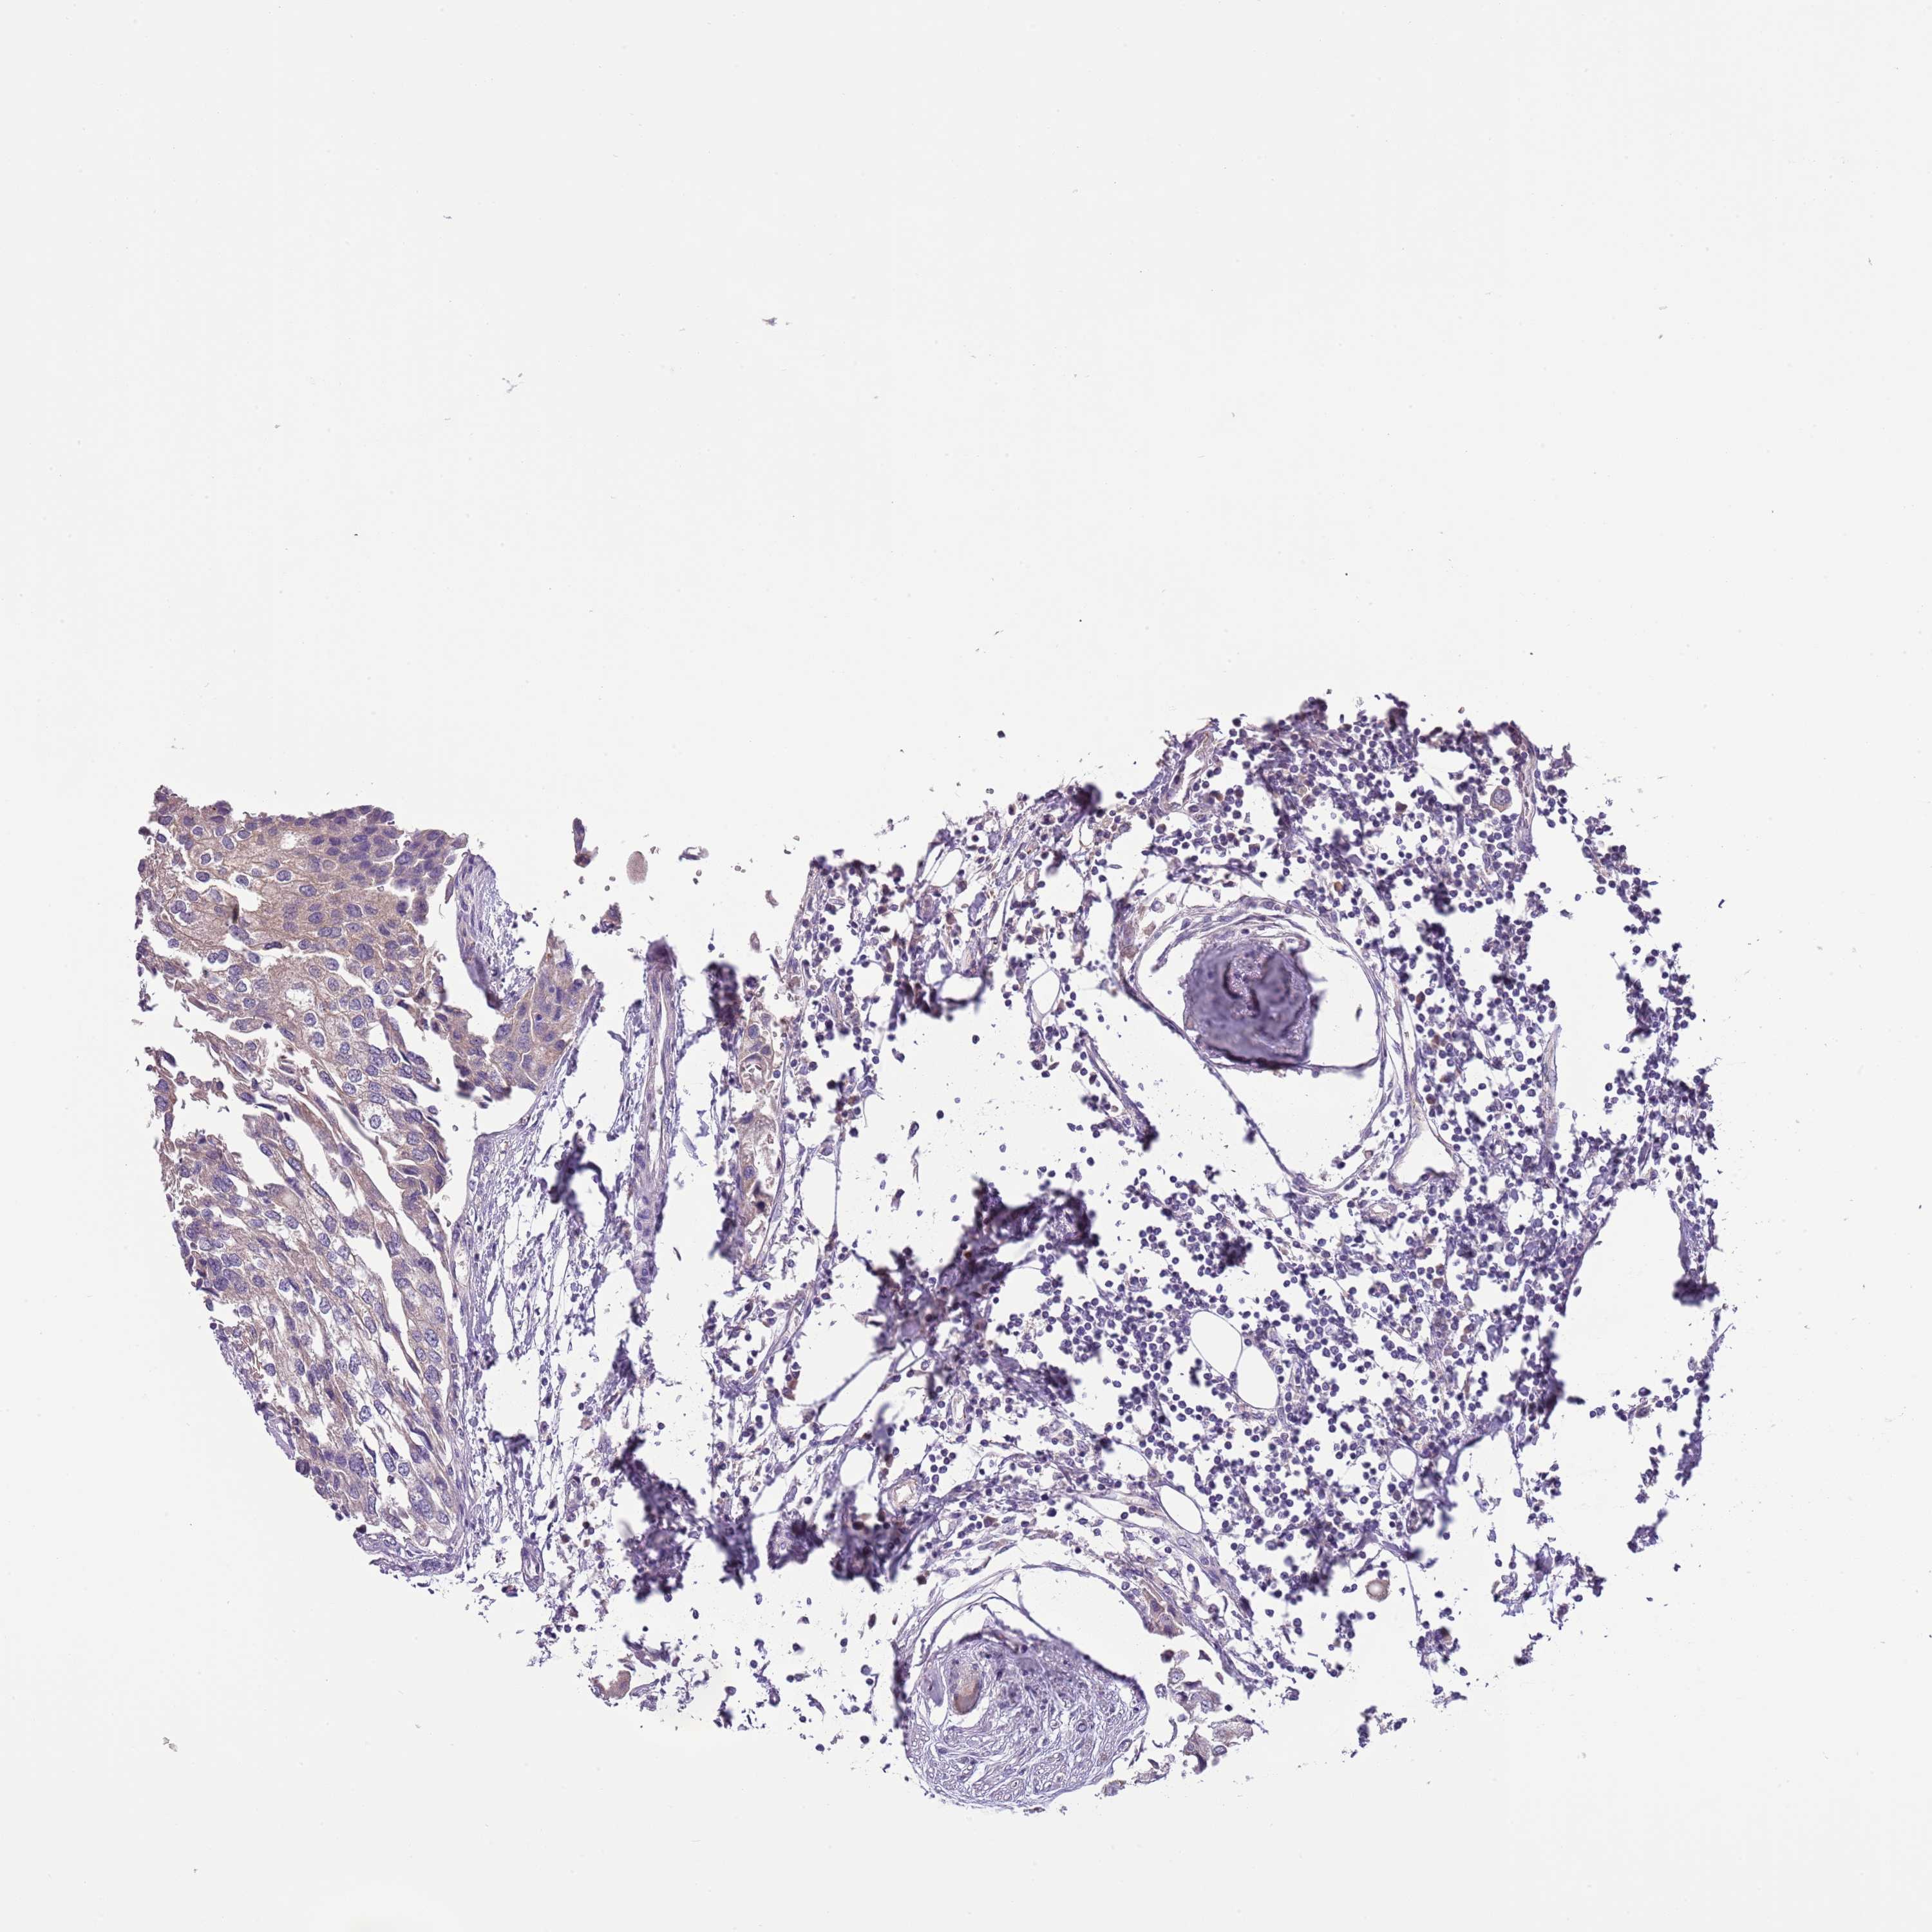

UROTHELIAL CANCER - Protein expressioni

A mouse-over function shows sample information and annotation data. Click on an image to view it in a full screen mode. Samples can be filtered based on level of antibody staining by selecting one or several of the following categories: high, medium, low and not detected. The assay and annotation is described here.

Note that samples used for immunohistochemistry by the Human Protein Atlas do not correspond to samples in the TCGA dataset.

Antibody stainingi

Antibody staining in the annotated cell types in the current human tissue is reported as not detected, low, medium, or high, based on conventional immunohistochemistry profiling in selected tissues. This score is based on the combination of the staining intensity and fraction of stained cells.

Each image is clickable and will lead to virtual microscopy that enables deeper exploration of all samples and also displays staining intensity scores, fraction scores and subcellular localization as well as patient and tissue information for each sample.

Antibody HPA047927

Staining

High

Medium

Low

Not detected

Intensity

Strong

Moderate

Weak

Negative

Quantity

>75%

75%-25%

<25%

None

Location

Nuclear

Cytoplasmic/membranous

Cytoplasmic/membranous,nuclear

Urothelial carcinoma, High grade

Urothelial carcinoma, Low grade

Urothelial carcinoma, NOS